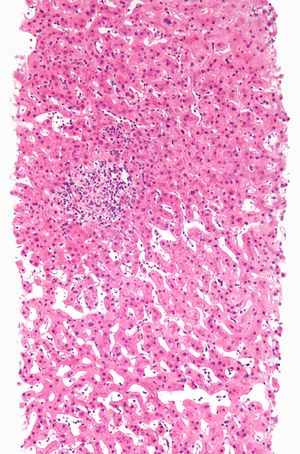

약물로 인한 간 손상의 구체적인 조직병리학적 양상은 다음과 같다.

'''간염''' (Hepatitis)

간세포 괴사와 함께 염증 세포의 침윤이 동반되는 양상이다. 약물 유발성 간염은 다음 세 가지 유형으로 나눌 수 있다.

- 바이러스성 간염형: 가장 흔하며, 조직학적 특징이 급성 바이러스성 간염과 유사하다.

- 원인 약물: 할로세인, 이소니아지드, 페니토인

- 국소성 또는 비특이성 간염: 산재된 세포 괴사 부위에 림프구 침윤이 동반될 수 있다.

- 원인 약물: 아스피린

- 만성 간염형: 임상적, 혈청학적, 조직학적으로 자가면역간염과 매우 유사하다.

- 원인 약물: 메틸도파, 디클로페낙